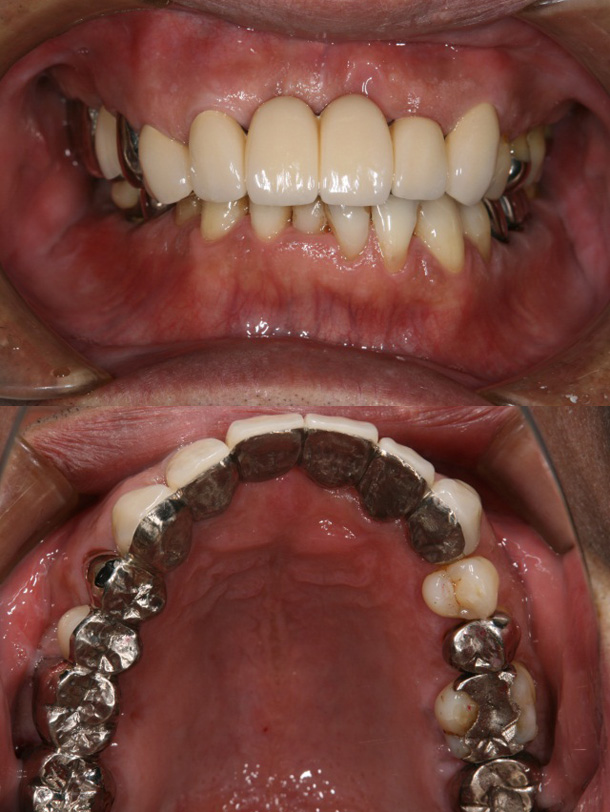

症例6:叢生による矯正治療後、上顎前歯・臼歯部をオールセラミッククラウンにて審美修復した症例

主訴:右下の冠がはずれた、前歯で咬めない

年齢:43歳

診断:上顎前歯酸蝕症による舌側エナメル質欠損、上下顎叢生、臼歯部反対咬合

装置:上下顎ブラケット装置

治療期間:2年1ヶ月(矯正治療)(来院回数24回)

抜歯:右下顎大臼歯の2本(むし歯によ)保存不可のため→インプラント治療を実施)

費用:750,000円+税

矯正前

矯正後

オールセラミックSET後

口元の変化